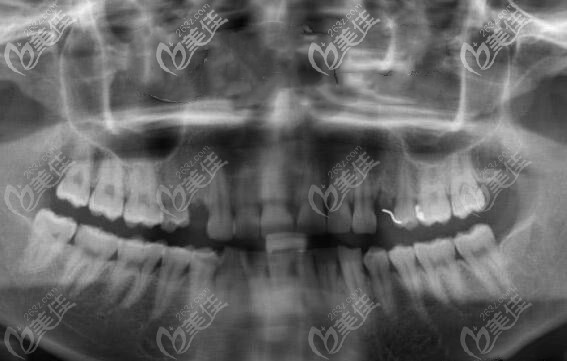

制定方案后,就帮顾客免费拍了口腔CT全景片,从CT片中可以看出来有单颗缺失,但是牙槽骨条件良好,无炎症,做种植也比较简单,性价比比较高的韩国登腾种植体就可以做。

天津雅尔美口腔的医生就利用数字化电脑进行了简单的设计,避开血管神经,确种植体的位置,以及种牙后的牢固性。确方案后就开始手术。